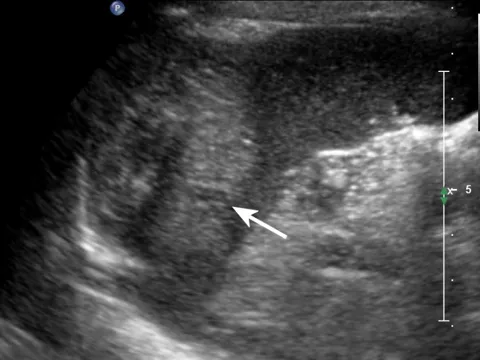

灰阶超声,脾破裂,显示脾实质内见低回声不均匀区,边界不规则(箭头所示) 。